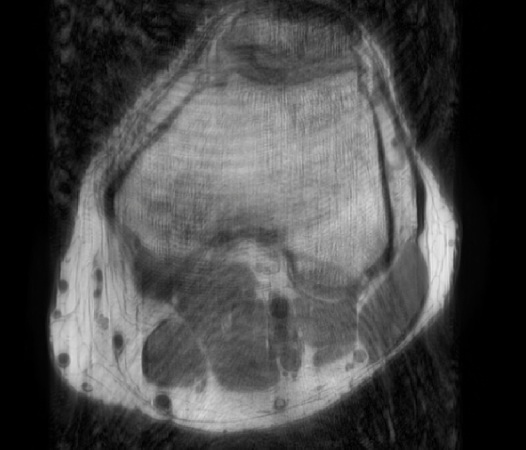

In the example below, only one fifth of the required MR radiofrequency signals is recorded. This results in a five times faster acquisition, with a subsampled k-space (top left) and inherent image artifacts after standard reconstruction (top right).

Philips Compressed SENSE

The Compressed SENSE reconstruction then uses iterative, knowledge-based algorithms to fill in the empty lines in k-space (bottom left). This removes the artifacts while keeping the final image fully consistent with the acquired data (bottom right). *Compared to Philips MR exams without Compressed SENSE